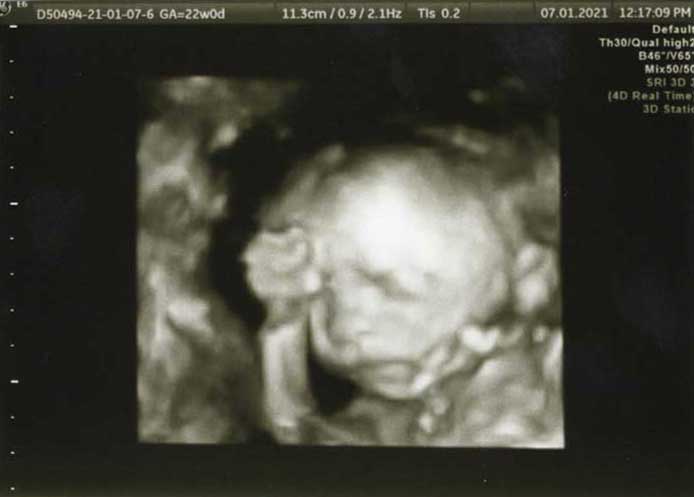

3D/4D HD LIVE

Στο ιατρείο μας προσφέρουμε υψηλής ευκρίνειας 3D και 4D τεχνολογία απεικόνισης του εμβρύου. Η τεχνολογία αυτή αποτελεί ένα ακόμα σημαντικό διαγνωστικό όπλο στη φαρέτρα του προγεννητικού ελέγχου, ενώ ταυτόχρονα ενισχύει την ανάπτυξη του δεσμού ανάμεσα στους μελλοντικούς γονείς και το μωρό τους.